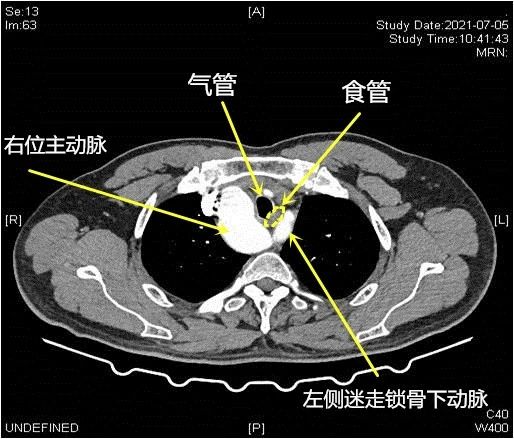

潘小杰主任说,正常人的主动脉弓都是在胸腔的左侧,而老廖的主动脉弓则长反了,长在右侧。这并不是简单的左右对调,而是会合并一系列的大血管畸形,导致胸腔内的血管、神经等都不在正常的解剖位置,这大大增加了食管癌手术的难度。

▲食管、异位主动脉弓及其上纵隔变异大血管关系示意图

他进一步解释说,目前主流的食管癌手术,都是通过右胸来游离食管,但由于老廖是右位主动脉弓,把食管全部推向左侧,右边则有主动脉弓的遮挡,所以只能从左侧进胸。这样一来,手术中医生就要面临更多的挑战。

首先,上胸段食管的游离困难。在上纵隔,由于食管被左侧颈总动脉、锁骨下动脉和气管包绕,导致上胸段食管的游离非常困难。

其次,左侧喉返神经常规是发自左迷走神经并钩绕主动脉弓而形成,但由于主动脉弓解剖位置的变异,对左侧喉返神经的探查、游离并保护变得相当困难。若稍有不慎,损伤到喉返神经,将造成患者声音嘶哑,甚至呼吸困难,危及患者生命。

最后,食管癌切除后,替代食管的管状胃如何上提至颈部并进行吻合,这也是医生要面临的新挑战。常规的食管癌手术,管状胃是经食管床上提至颈部并进行吻合,然而由于左迷走锁骨下动脉和气管之间的食管床间隙狭小,该患者无法按常规路径上提管状胃。